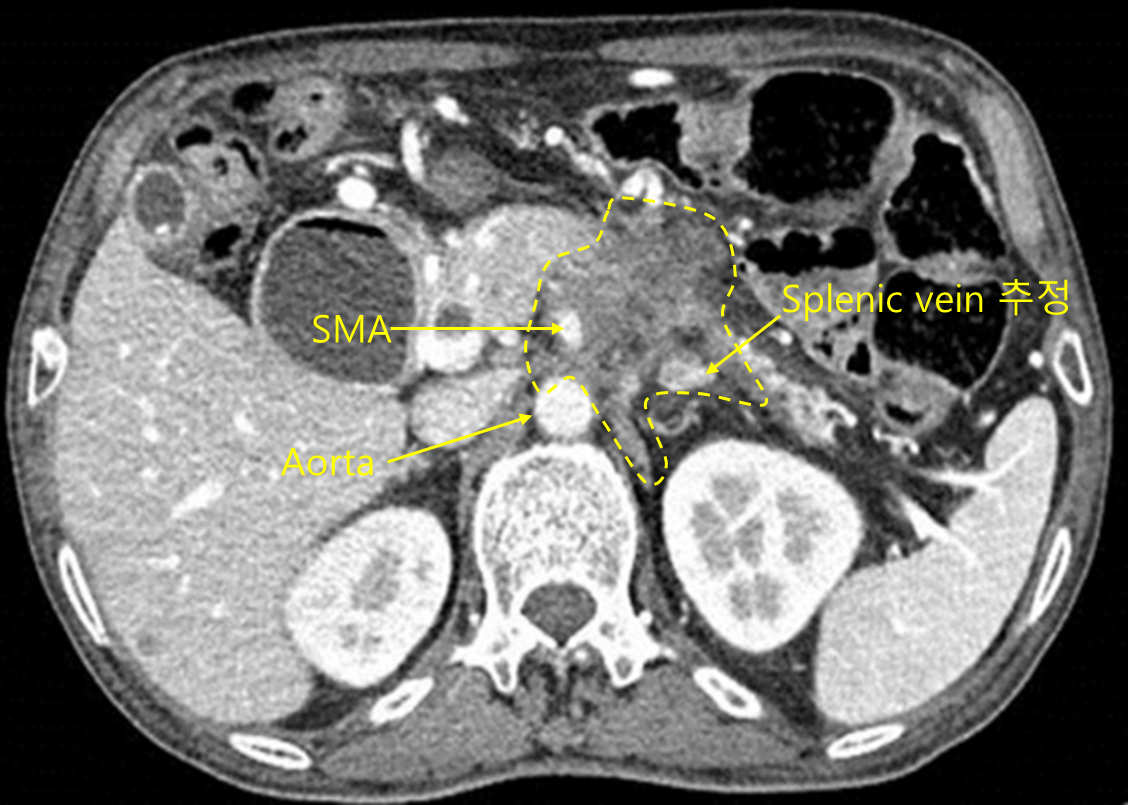

Img | CT: Pancreatic mass, with duodenal dilatation, possible mesentery and vessel invasion |

• CT상 췌장 가운데에 cancer로 추정되는 mass가 보이며, 일부는 mesentery와 mesenteric vessel까지 침범한 것으로 보인다. 따라서 unresectable한 pancreatic cancer의 가능성이 높다.